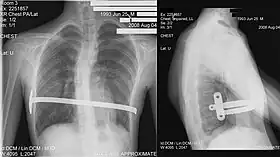

His two-stage procedure, widely known as the Nuss procedure, involves slipping in one or more concave steel bars into the chest, underneath the sternum.[56]

The bar is flipped to a convex position so as to push outward on the sternum, correcting the deformity. The bar usually stays in the body for about two years, although many surgeons are currently moving toward leaving them in for up to five years. When the bones have solidified into place, the bar is removed through outpatient surgery.

Although initially designed to be performed in younger children of less than 10 years of age, whose sternum and cartilage is more flexible, there are successful series of Nuss treatment in patients well into their teens and twenties.[57]

The Ravitch technique is an invasive surgery that was introduced in 1949[51] and developed in the 1950s. It involves creating an incision along the chest through which the cartilage is removed and the sternum detached. A small bar is inserted underneath the sternum to hold it up in the desired position. The bar is left implanted until the cartilage grows back, typically about six months. The bar is subsequently removed in a simple outpatient procedure; this technique is thus a two-stage procedure.

The Ravitch technique is not widely practiced because it is so invasive. It is more often used in older individuals, where the sternum has calcified when the deformity is asymmetrical, or when the less invasive Nuss procedure has proven unsuccessful.[52]